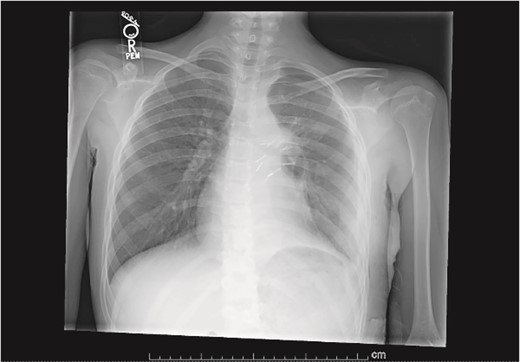

Our patient is a 10-year-old Caucasian female with a history of early adrenarche, ADHD, and COVID-19 and no past surgical history. She presented to the ED with a month-long history of persistent coughing, shortness of breath on exertion and speaking, and left-sided chest pain that began after a diagnosis of mildly symptomatic COVID-19. A physical exam revealed decreased breath sounds on the left, with a left-sided chest protrusion. A plain film and CT demonstrated a normal right lung, with a significant mediastinal shift toward the right, displacement of the heart into the right hemithorax, with complete whiteout of the left hemithorax, and demonstrating a mix of solid and cystic foci, with a round opacification at the left lung base (Figs 1 and 2). The patient underwent an uncomplicated left thoracotomy with excision of two masses, one being 22.5 × 21.0 × 10.5 cm and the other being 13.5 × 11.5 × 6.2 cm. These masses weighed 2394 g in aggregate. The specimens consisted of well-encapsulated tumors attached to the posterior aspect of the chest wall. A regional, positive lymph node measuring 3.0 × 2.2 × 1.0 cm was also resected. Due to the large size of the tumor and the requirement for clean margins, parts of the latissimus dorsi and serratus anterior muscles were also resected. By postoperative day (POD) 0, the left lung had already filled the left hemithorax, and the mediastinal shift had corrected (Fig. 3). The chest tube was removed on POD 5, and a plain film showed continued expansion of the lung to full size and resolving pulmonary edema and atelectasis (Fig. 4). The patient was discharged home on POD 5. The tumor staging was T4N1M0. The tumor was positive for vimentin, CD56, synaptophysin, chromogranin, and NSE. The tumor was negative for pancytokeratin, Cam5.2, EMA, S100, desmin, SMA, SOX10, HMB45, CD117, DOG1, CD99, PR, CD68, WT1, CD30, p53, Alk1, GFAP, and nuclear β-catenin. Next-generation sequencing showed an MGA:NUTM1 fusion, supporting a final diagnosis of high-grade MGA:NUTM1 fusion SCS. Given the size and grading of the tumor, the patient underwent adjuvant CT-RT with ifosfamide, doxorubicin, and proton beam radiotherapy, with supportive doses of MESNA and dexrazoxane for 4.5 months post-operatively. The basis of this treatment is ARST0332 Arm C [6]. Before treatment initiation, the patient underwent an uncomplicated left oophorectomy for reproductive cryopreservation. A PET/CT prior to CT-RT showed hypermetabolic activity in several areas. These included the pleural resection margin, a mediastinal lymph node concerning for metastasis versus postsurgical change, and a left axillary lymph node concerning for metastatic disease. During treatment, the patient contracted human metapneumovirus and rhino/enterovirus, resulting in febrile neutropenia. The patient was successfully treated with blood and platelet transfusions and pegfilgrastim. Upon completion of CT-RT, PET/CT imaging showed no evidence of residual disease, with minimal focal hypermetabolic activity as compared to the previous imaging (Fig. 5).

Plain film postoperative day 5, after removal of chest tube, showing improving pulmonary status in the left hemithorax.